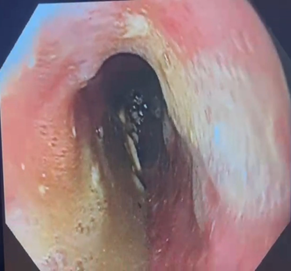

After comprehensive rehabilitation, a methylene blue test identified leakage below the LAMS. A new 12 cm LAMS was inserted, covering the leak and the patient remained on NPO status with enteral nutrition. After 28 days, the LAMS were removed, and no leakage was detected. An esophagogram confirmed an anastomotic fistula (Figure 3), and a new defect measuring 10 mm was managed with a new E-VAC system. The E-VAC system required 9 replacements, but the fistula persisted at a reduced size of 7 mm. Fibrin sealant was used for management. The patient resumed oral feeding after deglutition rehabilitation and showed improved dysphagia. During the last endoscopic follow-up, no leaks or fistulas were observed, indicating a successful procedure (Figure 4).

Figure 4 Anastomotic junction without signs of anastomotic leak or anastomotic fistula.